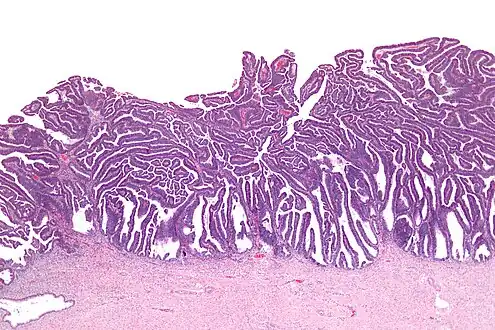

The name of the lesion describes it microscopic appearance. It has nipple-like structures with fibrovascular cores (papillae) that are long in relation to their width (villus-like), which are covered with a glandular pseudostratified columnar epithelium.

Micrograph of a villoglandular adenocarcinoma the cervix. H&E stain.

Intermediate magnification